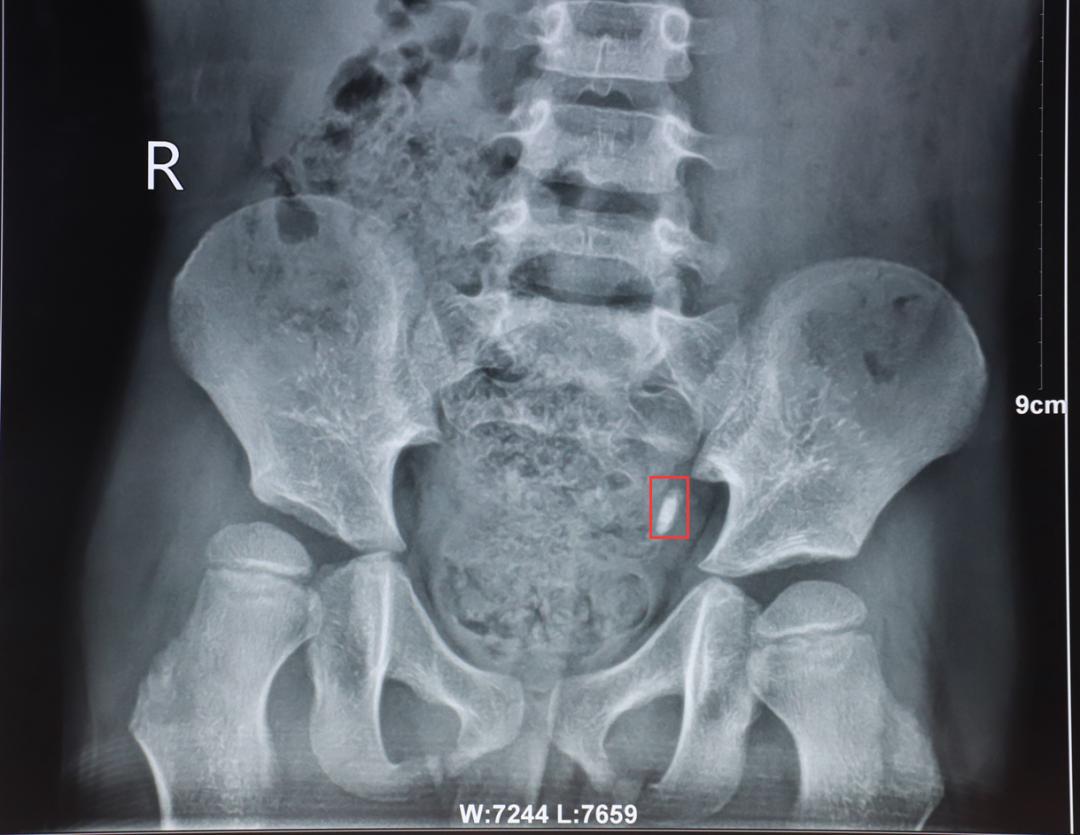

△ 梗阻在患者左侧输尿管内的结石影像

在贵阳结石病医院,检查结果显示,一颗1厘米左右的结石梗阻在小宇左侧输尿管内,导致孩子的左侧肾脏出现了轻度积水。